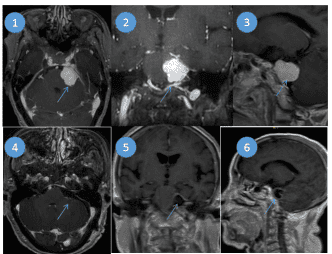

颅底脑膜瘤切除术(岩斜脑膜瘤):该部位肿瘤毗邻脑干,重要神经,血管,我科有非常成熟的手术技术以及经验,在电生理监测下,显微镜下微创切除肿瘤,图①②③为术前肿瘤(箭头),图④⑤⑥为术后完全切除后的影像检查结果。